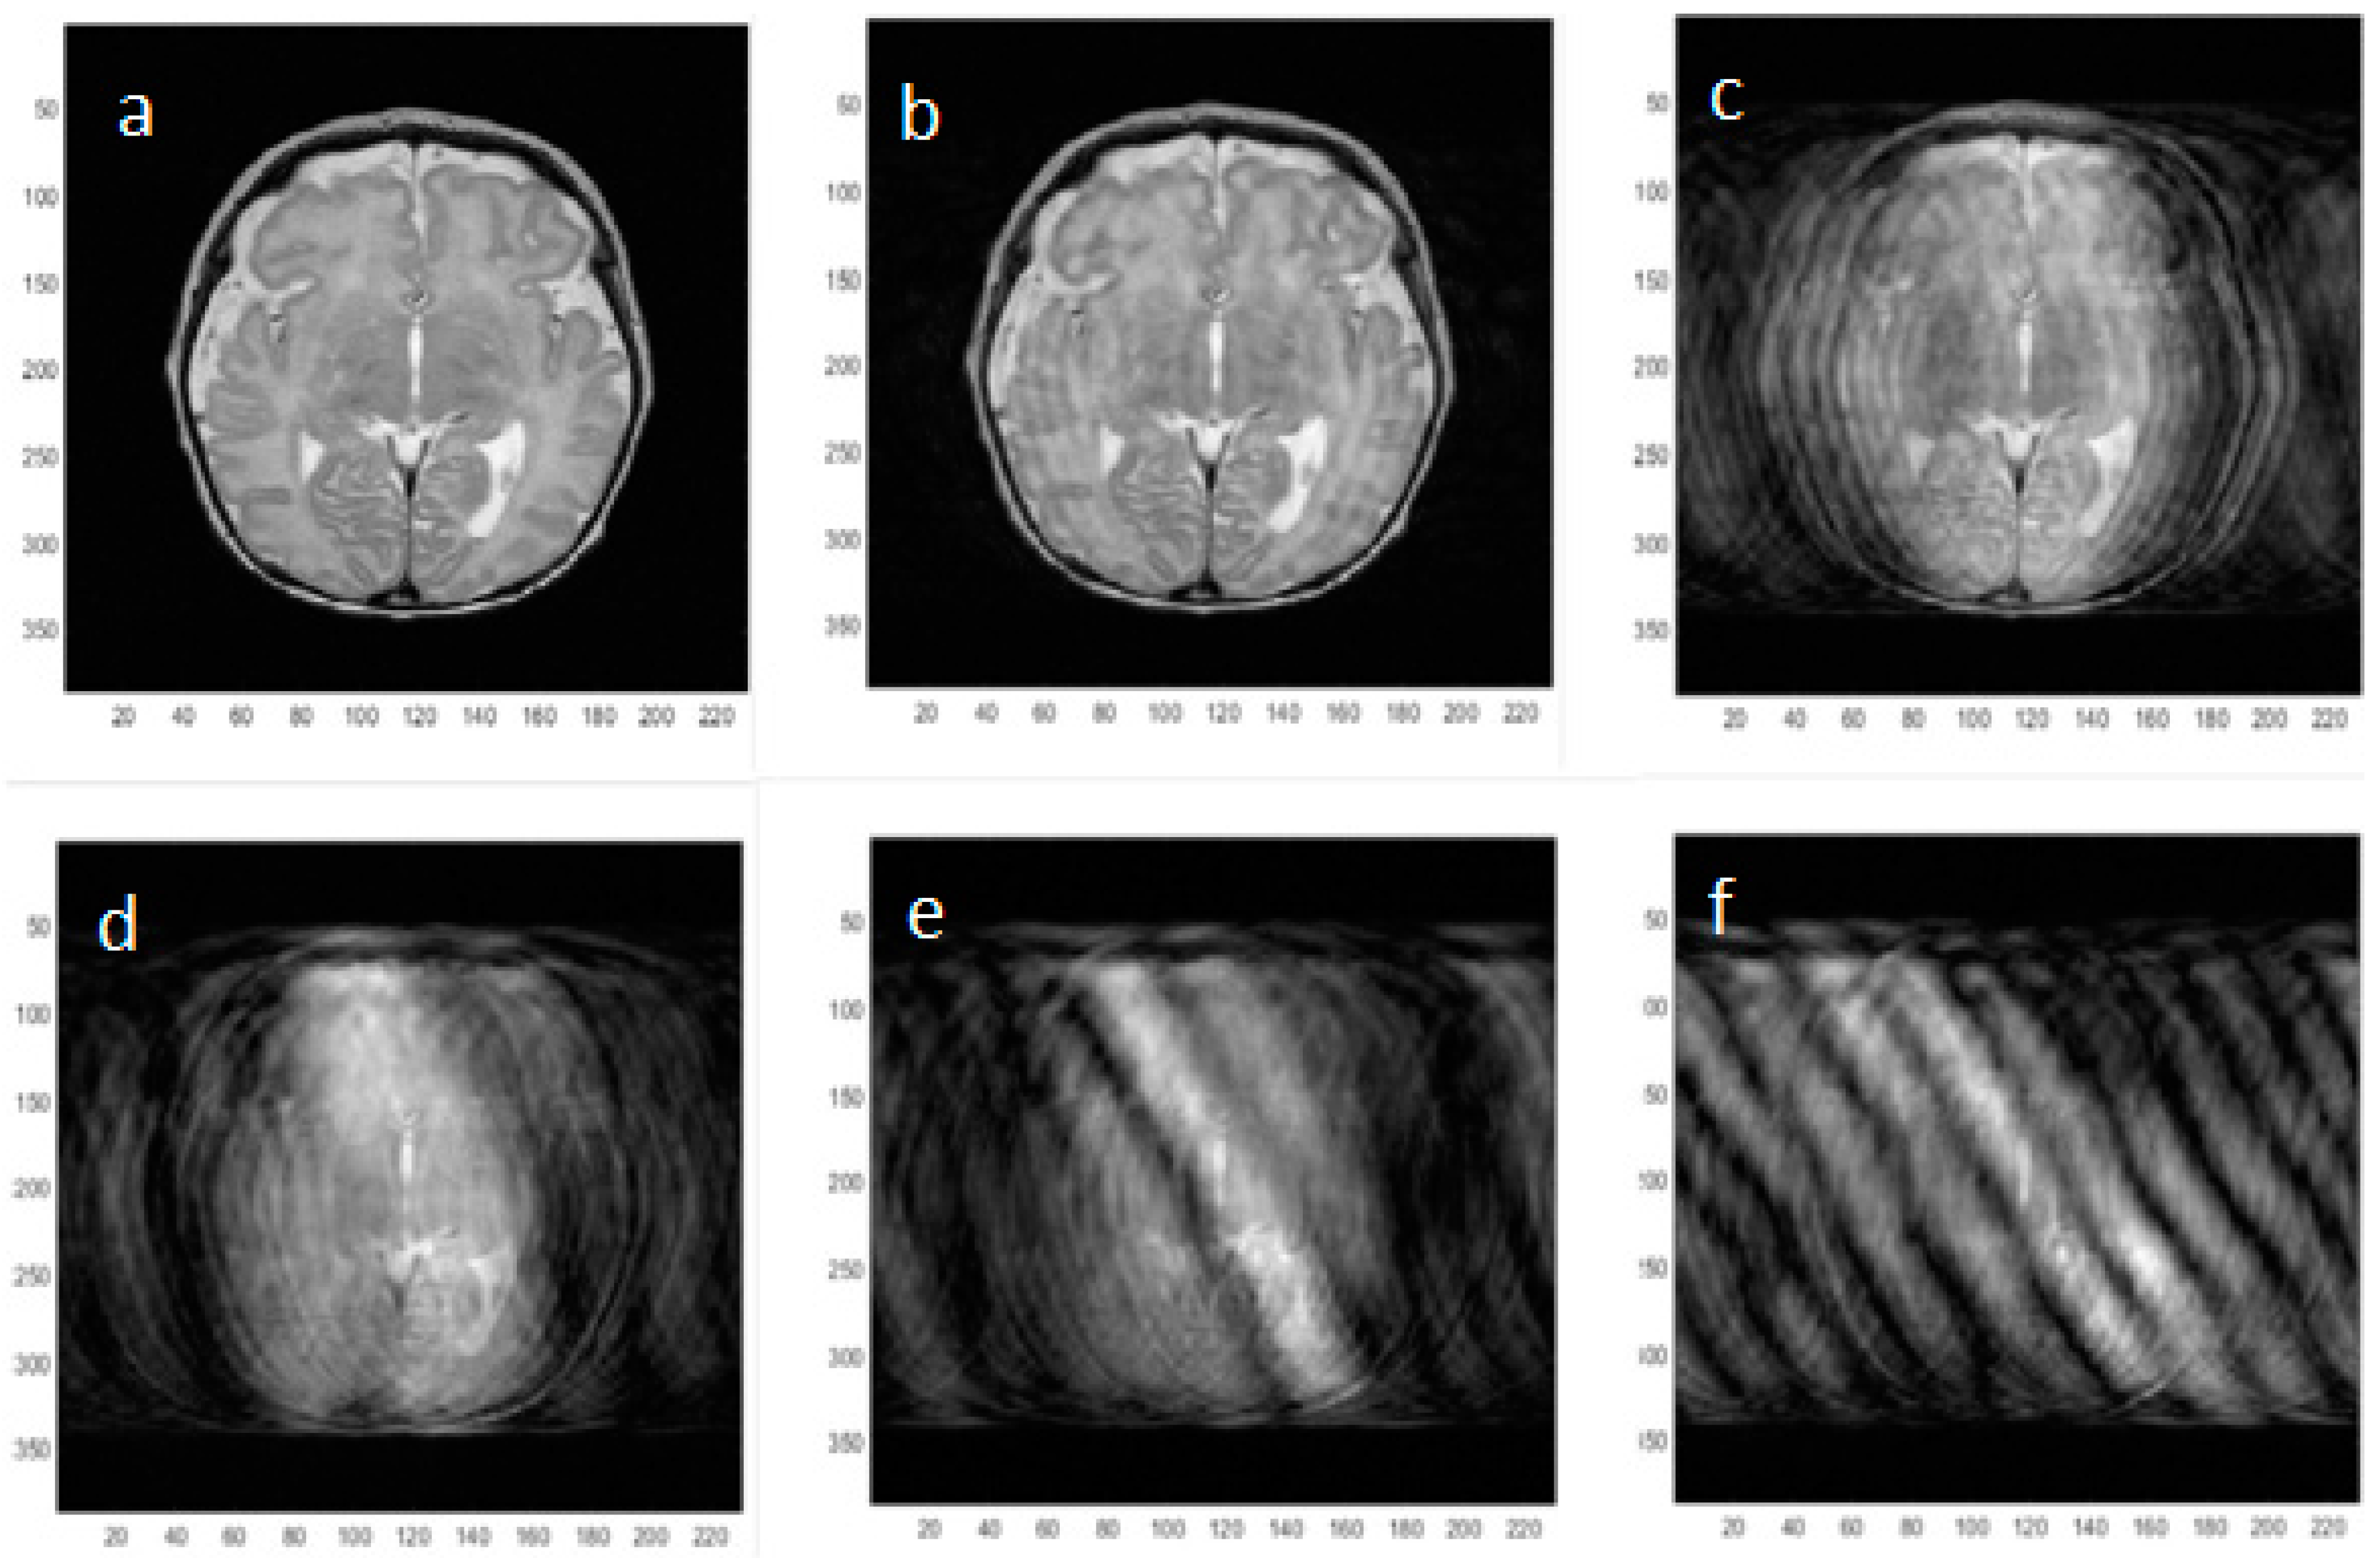

To better understand the effects of rotational motion on neonatal MR images, artifacts were simulated using a measurement of angular in-plane motion acquired using the accelerometer applied to an image k-space data set acquired with no motion artifacts. A measured motion file was downsampled to match the number of phase encoding steps and the k-space locations rotated accordingly (Figure 5). Following image reconstruction of the rotated data sets, the image artifacts created by successively doubling the amount of angular rotation applied were assessed visually.

Figure 6. Simulated neonatal axial MR images incorporating increasing amounts of in-plane pseudo-sinusoidal angular motion (alpha) as shown in Figure 5. The original image with no motion artifact is shown in (a) and then the peak-to-peak angular motion applied to the k-space locations is doubled in successive images (b) 2 × 10−2; (c) 4 × 10−2; (d) 8 × 10−2; (e) 1.6 × 10−1; (f) 3.2 × 10−1 radians to simulate neonatal head motion. A standard rotation matrix was used to multiply the k-space locations by the relevant measured angle. In principle, reversal of the motion effects by counter-rotating the k-space data according to the measured rotation angles should be possible.